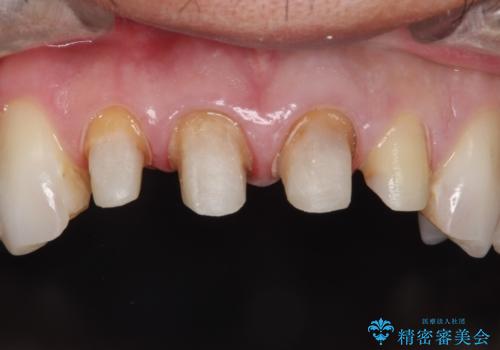

昔装着したかぶせ物を自然な色にしたい オールセラミックによる審美的改善

- 前歯のかぶせ物を自然な色味のものにしたいとのことで、来院されました。

保険適用のかぶせ物が装着されており、適合も悪く、変色している状態でした。

土台からの、再治療を行い、オールセラミッククラウンの装着を行う計画としました。

審美的な改善はもちろんのこと、ぴったりとしたものを装着することで、歯茎の発赤も改善されました。